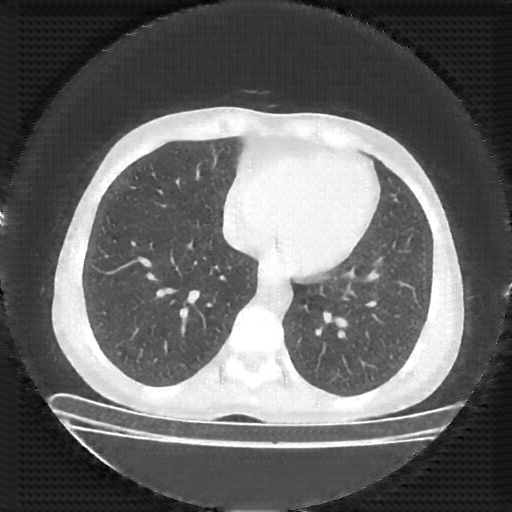

Original NATIVE CT scan (input)

No window - Raw intensity values

Lung window (WL -600, WW 1500 β†’ Low βˆ’1350, High +150)

Mediastinum window (WL 40, WW 400 β†’ Low βˆ’160, High +240)